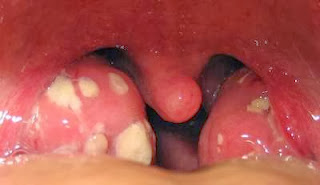

Viêm amidan mạn tính thường do biến chứng từ viêm amidan cấp tính nếu không chữa trị đúng cách tận gốc, diễn biến lặp đi lặp lại mà có. Biểu hiện chủ yếu là cổ họng hay có cảm giác ngứa, khô nóng, hơi đau. Có khi cảm giác như có dị vật, hôi miệng, sốt nhẹ, tiêu hóa kém, mất sức .

viêm amidan nếu để lâu không chữa trị hoặc chữa trị không đúng cách thì rất dễ biến chứng nguy hiểm thành những bệnh sau :

Trường hợp viêm amidan nhiều lần thường dẫn đến áp xe quanh amidan. Bệnh nhân đau họng, khó nuốt, sưng họng nói không ra tiếng, đau đầu, sốt cao, hơi thở hôi, chảy nước dãi, do không nuốt được.